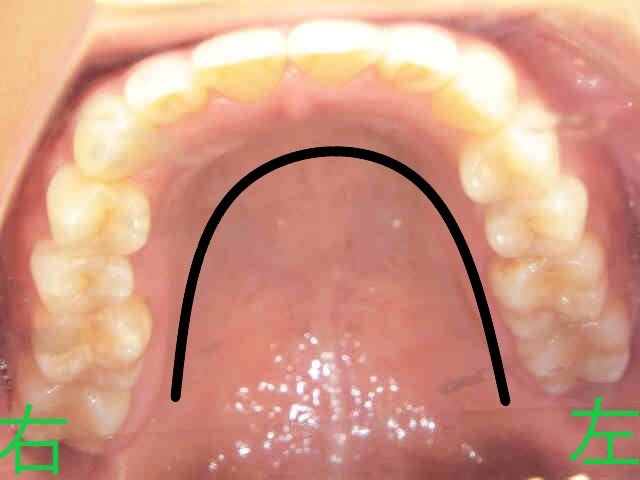

口腔内写真では、術前はV字型だった上顎歯列が、術後にはU字型に改善されている様子が確認できます。